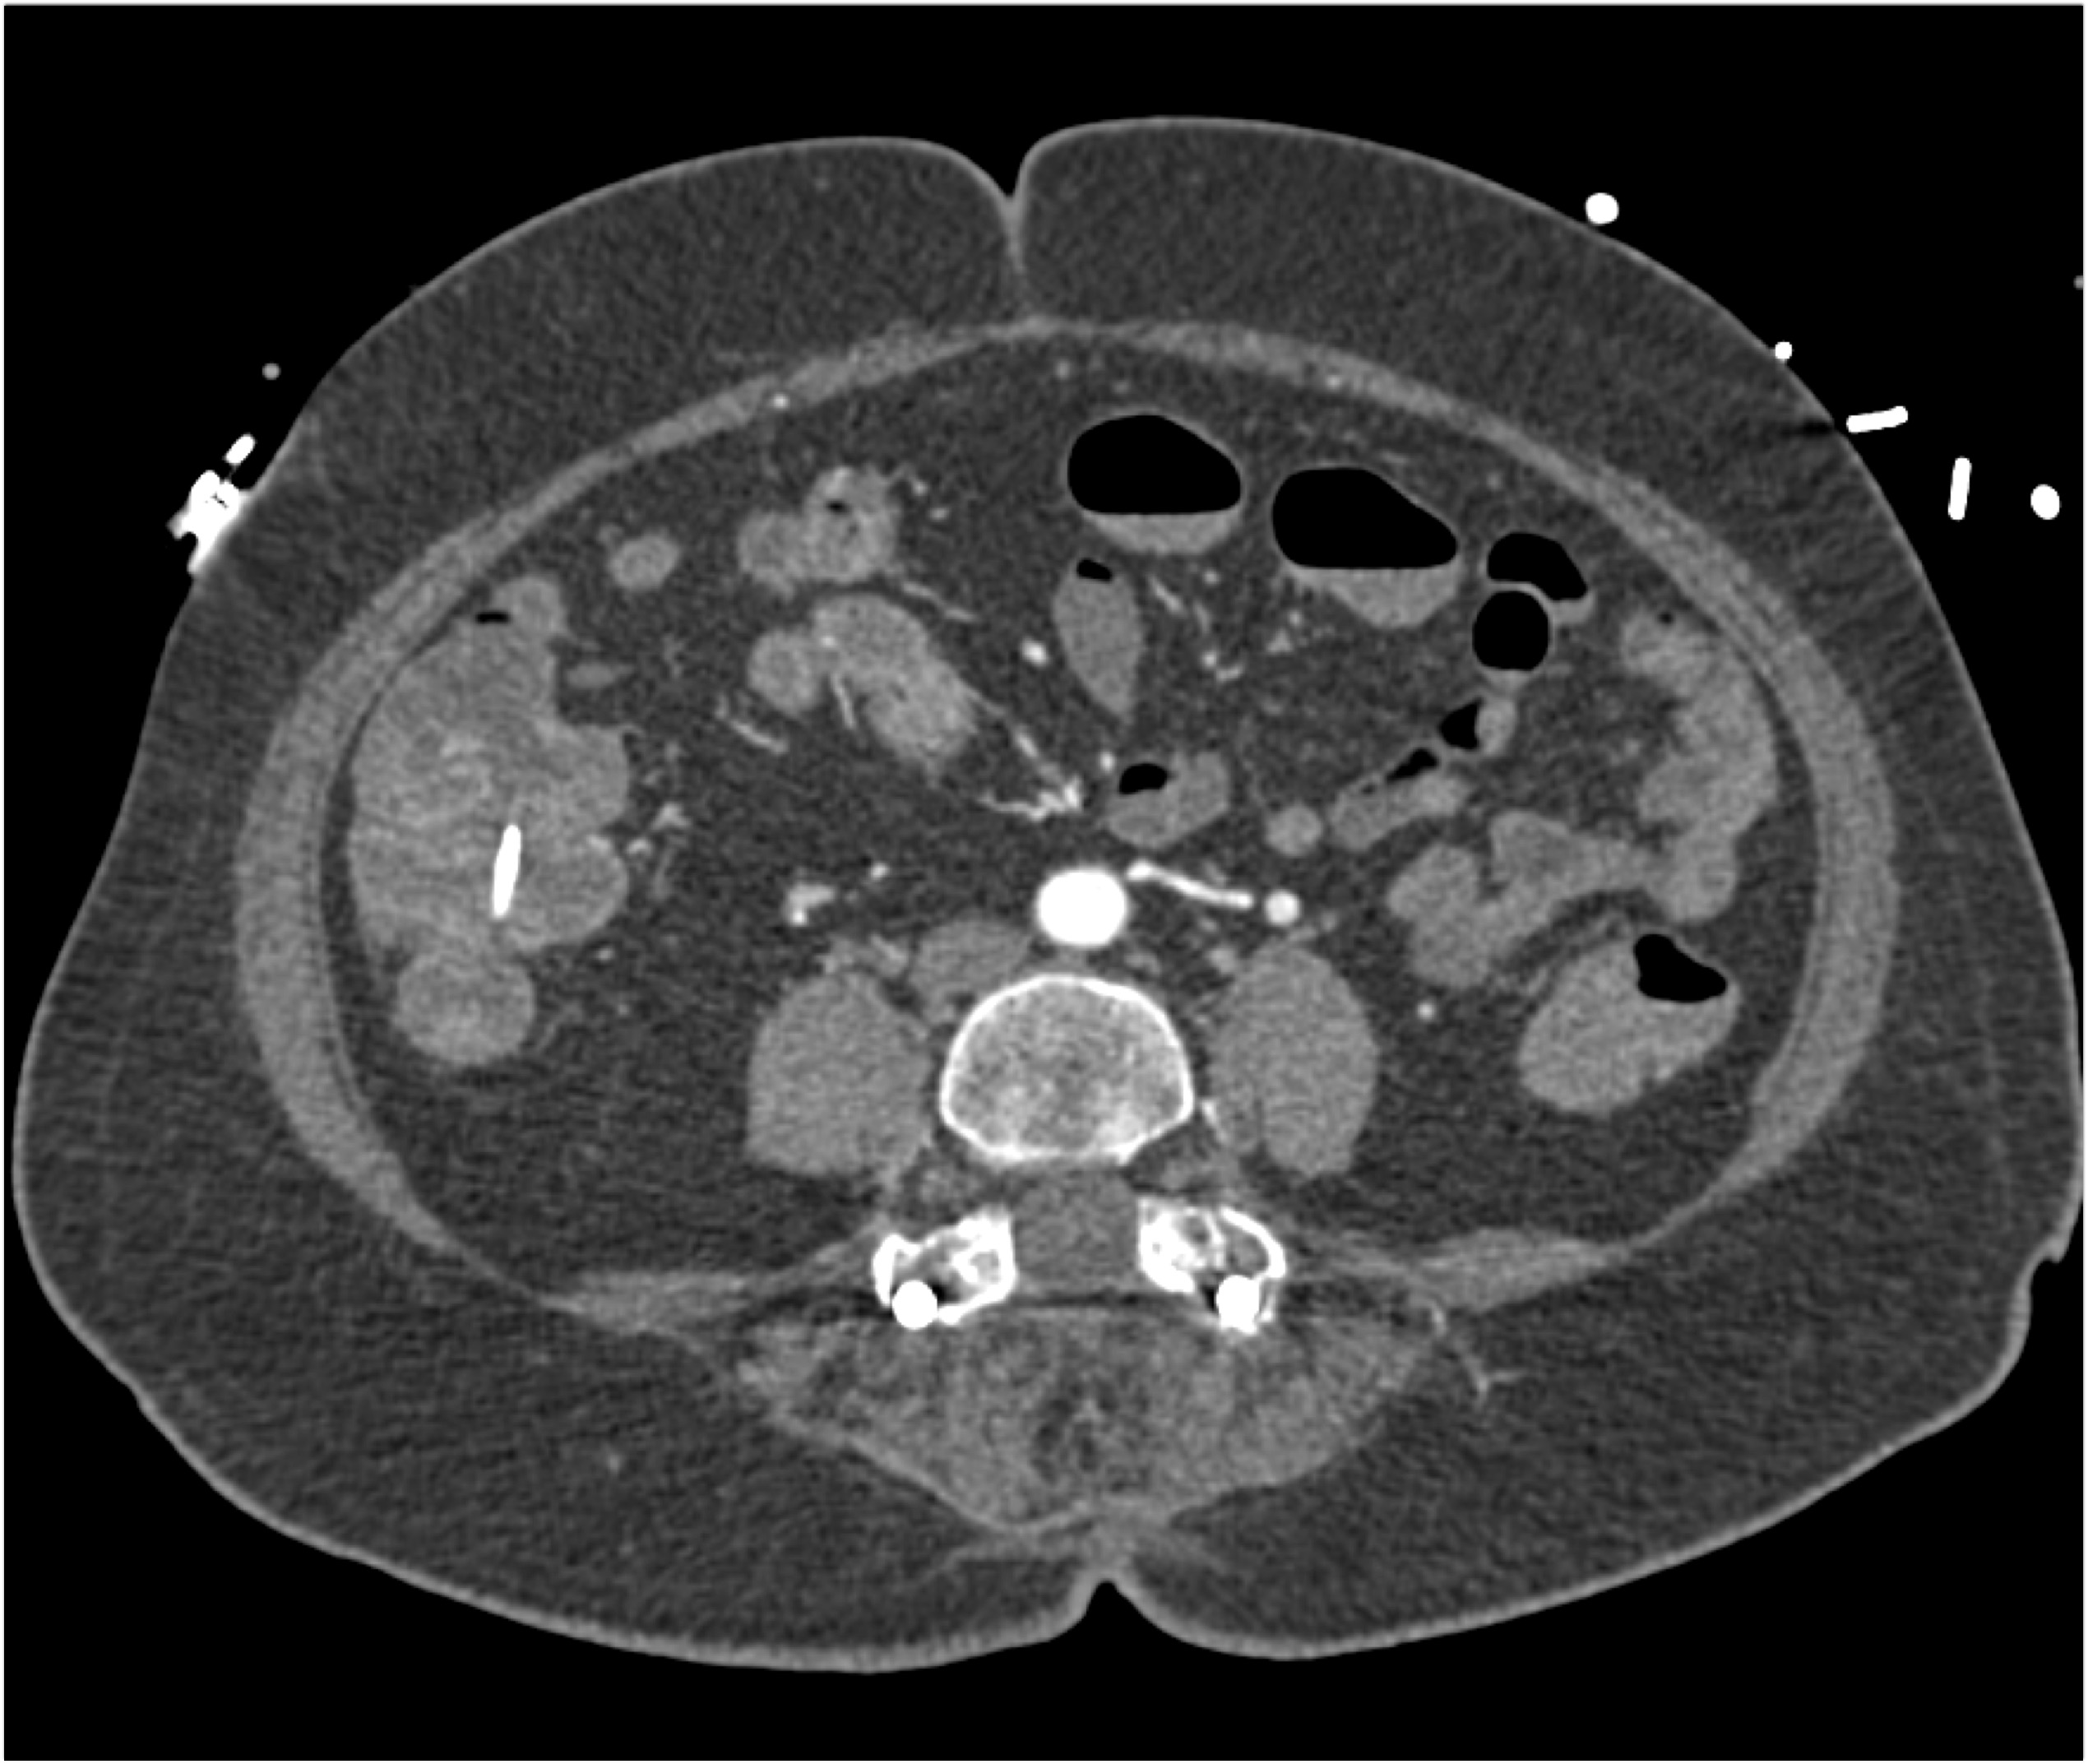

In this patient with abdominal pain post colonoscopy the key finding is?

pneumoperitoneum

splenic trauma

bleed in cecum following polyp removal

retroperitoneal bleed